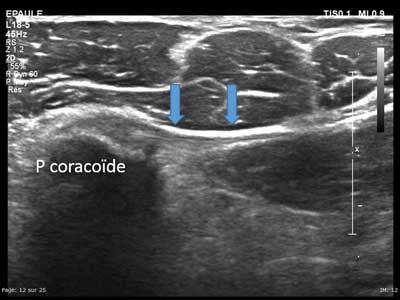

Figure 14

Axial view of the musculocutaneous nerve from the axillar area to the elbow (a to f). NMC: Musculocutaneous nerve, Coracobr: coracobrachial muscle, Hum: Humerus, Long Biceps: Long head of the biceps, Court biceps: short head of the biceps, Brachial: Brachial muscle, Brachio-radial: Brachio-radial muscle, VCEPH: Cephalic vein.